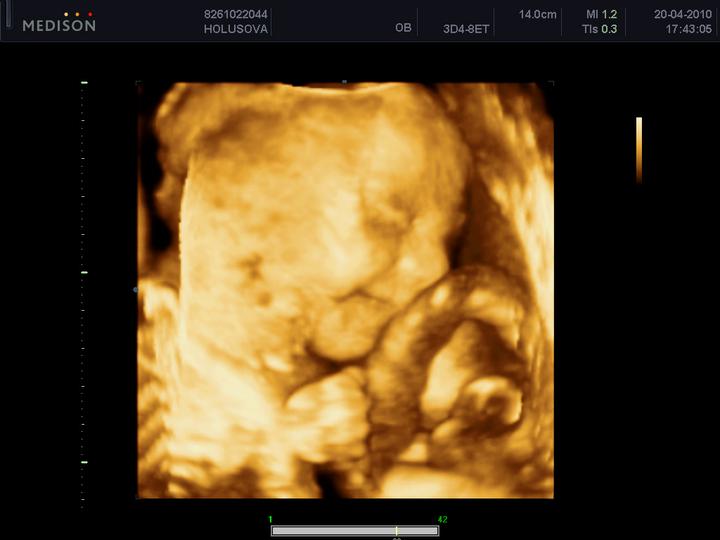

dne 8.7. se jedeme podívat na naše mimi na 3D ultrazvuk🙂